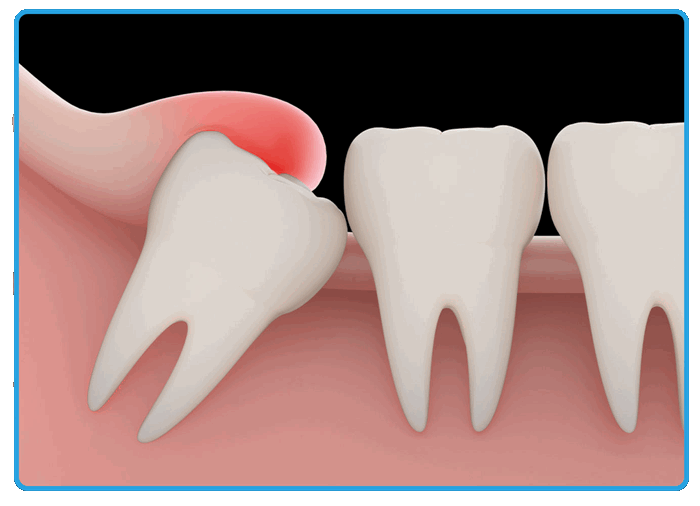

Одной из наиболее распространенных и вместе с тем травматичных операций на амбулаторном хирургическом приеме является удаление нижних зубов мудрости при их затрудненном прорезывании и недостатке места в зубном ряду. Удаление зачатков третьих моляров оптимально проводить в возрасте 15—16 лет, когда корень еще не сформирован, но подростку уже легче перенести эту манипуляцию в амбулаторных условиях.

Удаление зачатков третьих моляров оптимально проводить в возрасте 15—16 лет, когда корень еще не сформирован, но подростку уже легче перенести эту манипуляцию в амбулаторных условиях

Своевременно проведенное вмешательство позволяет избежать дальнейших проблем, предупреждает развитие воспалительных осложнений, помогает достичь оптимального и, самое главное, стабильного результата ортодонтического лечения при значительном дефиците места в зубном ряду. При планировании данной операции необходимо учитывать такие факторы, как глубина залегания зачатков, положение по оси (наклоны), отношение к соседнему зубу и нижнечелюстному каналу, количество и форма корней, стадия формирования корня, количество костной ткани, окружающей зуб, а также общее состояние здоровья [2, 3].